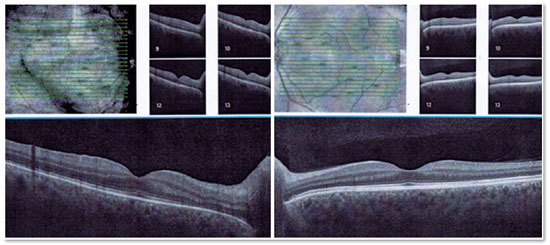

Ao exame, apresentava acuidade visual corrigida de 20/60 no olho direito (OD) e 20/20 no olho esquerdo (OE), biomicroscopia: precipitados ceráticos finos e RCA de 1+/4+, fácica no OD e sem alterações no OE. PIO normal em ambos os olhos e fundoscopia: nervo óptico borrado, lesão retiniana esbranquiçada de limites imprecisos e com hemorragias retinianas próximo à arcada temporal inferior no OD (Figura 1A, 1C e 2A) e sem alterações no OE (Figura 1B e 1D).

A tomografia de coerência óptica (OCT) da mácula demonstrou atenuação da depressão foveal e aumento da espessura retiniana com a presença de pequenos espaços hiporrefletivos no OD e presença de edema em nervo óptico (Figura 3). Foi mantido a dose de ataque de Ganciclovir endovenoso e a paciente foi reavaliada com 15 dias, porém a lesão permaneceu com sinais de atividade e a paciente iniciou quadro de leucopenia persistente. Então, foi suspendo o Ganciclovir endovenoso e realizadas 2 injeções intravítreas de Ganciclovir na dose de 2mg/0,1ml com intervalo de 15 dias. Após 15 dias da última aplicação, ela apresentou acuidade visual corrigida de 20/25, sem RCA, nervo óptico com bordas mais definidos e lesão retiniana de bordas regulares com aspecto cicatricial e sem hemorragias no OD (Figura 1E e 2B). O OCT de mácula demonstrou depressão foveal fisiológica e ausência de espaços hiporrefletivos (Figura 4). Após 3 meses da injeção intravítrea, permaneceu sem sinais de recidiva.